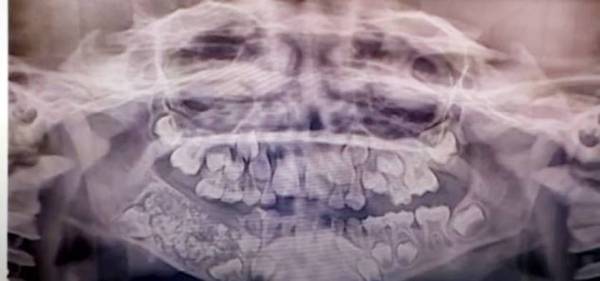

أعلن أطباء، أمس الأول (الأربعاء)، اقتلاعهم نحو 526 سنا وضرسا ونابا من فم طفل عمره 7 سنوات، يعاني من حالة طبية استثنائية.

ووفقا لوكالة «رويترز»، يعاني الطفل من ورم في الجانب الأيمن من الفك السفلي له منذ كان عمره 3 سنوات. وأظهر فحص طبي أجراه جراحون وجود نمو كبير يحتوي على هياكل صلبة متعددة في الفك.

وقال الأطباء إن هذه حالة طبية فريدة من نوعها، يتم وصفها بأنها «ورم مركب بالأسنان». يذكر أنه في عام 2014، تم اقتلاع 232 سنة من فم مراهق في مومباي بالهند أيضا.